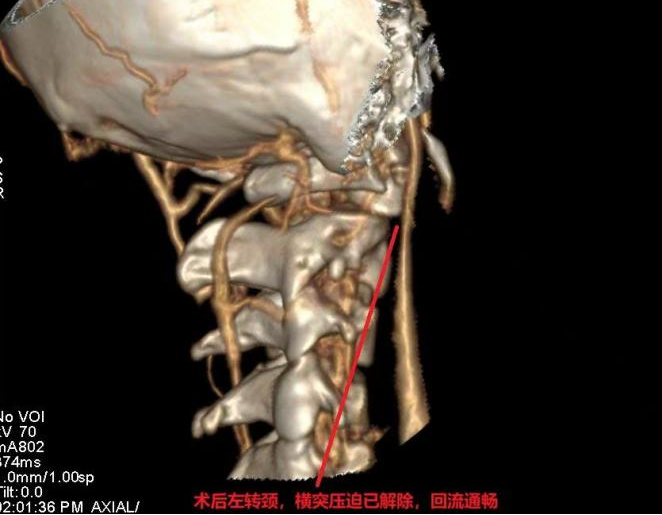

手术区域毗邻颈椎、重要神经、颈部大血管,风险极高。为确保手术安全有效,神经外科(金山病区)脑血管亚专业组与脊柱脊髓亚专业组强强联合,为患者实施了精准手术。经过数小时鏖战,成功完成了西南地区首例寰椎横突部分磨除联合颈内静脉减压术!

术后两周,患者脑鸣、头痛彻底消失;术后复查显示右侧颈内静脉压迫已完全解除,静脉恢复良好,血流在各种姿势下均通畅无阻。